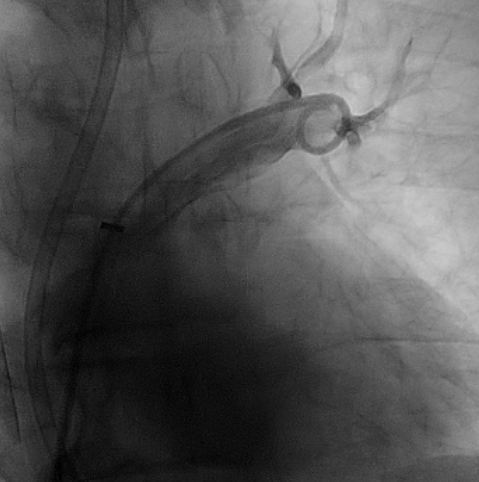

Pulmonary ArteriographyPA Pressure 55/26/36 mmHg. Pulmonary Arteriogram: Massive filling defect at main pulmonary trunk and bilateral pulmonary arteries (PA).Successful mechanical thrombectomy was performed under VA-ECMO Coronary AngiogramLMS: Mild diseaseLAD: Occluded from pLAD segment onward, retrograde from right systemLCx: Co-dominant, diffuse disease, critical stenosis at mLCxRCA: Co-dominant, mRCA critical stenosis, retrograde to LAD

Index ProcedureUnder VA-ECMO support (right internal jugular vein and right common femoral artery approach), successful mechanical thrombectomy was performed on the right and left PA with Lightning 12 Aspiration Catheter, clot separator and Silverway guidewire. Repeat PA angiogram showed flow restoration and improved PA pressure 31/18/23 mmHg.The patient subsequently stabilised, Coronary Angiogram and staged PCI was arranged.